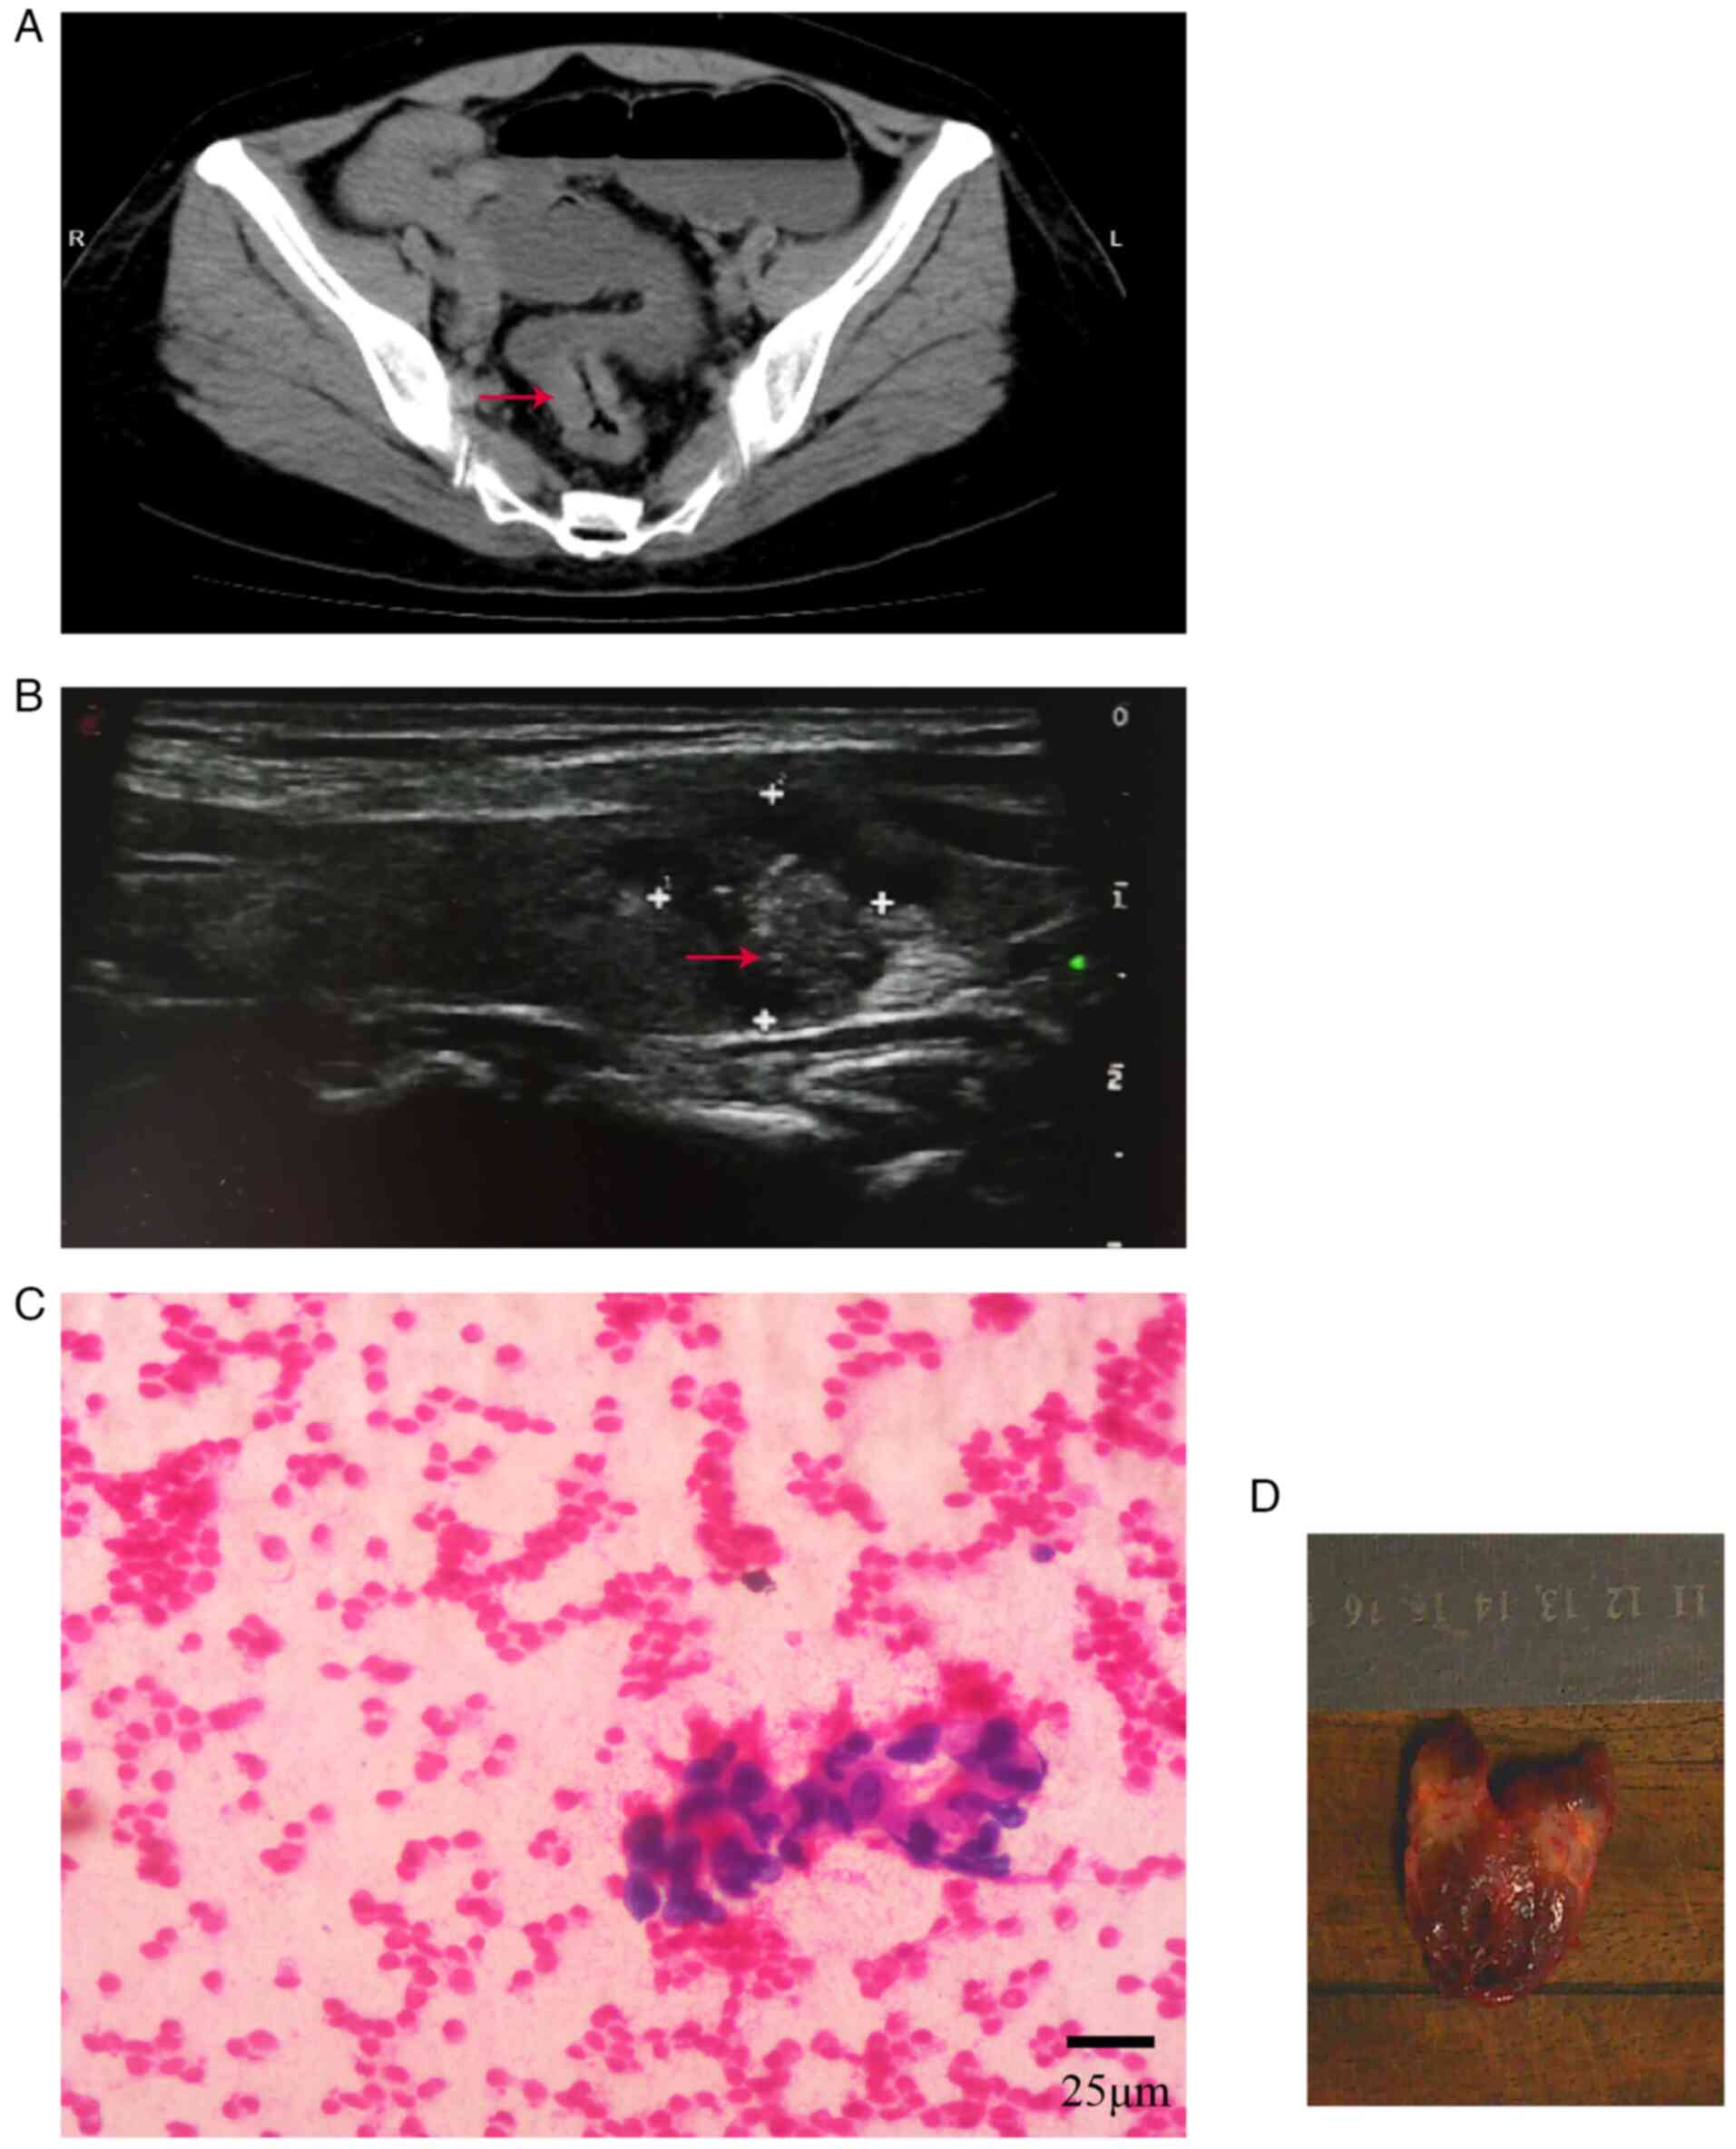

Metastatic thyroid cancer is rare. Here, the case of a patient with colon cancer that metastasized to the thyroid is described. The patient underwent radical rectal cancer surgery in August 2017 and received six cycles of chemotherapy with oxaliplatin and capecitabine postoperatively. On August 4, 2018, the patient was admitted to the hospital due to the discovery of thyroid nodules on ultrasound and carcinoembryonic antigen levels within the normal range. The biopsy from the fine needle aspiration suggested a malignant tumor. The patient underwent radical thyroid cancer surgery. Using intraoperative rapid frozen pathology, medullary carcinoma was diagnosed. Using postoperative routine pathology combined with immunohistochemistry results, thyroid metastasis from colorectal adenocarcinoma was diagnosed. After surgery, the patient regularly visited the outpatient clinic for chemotherapy with capecitabine. As of May 2023, the patient is still alive with no recurrence.

Figure 2

Figure 3